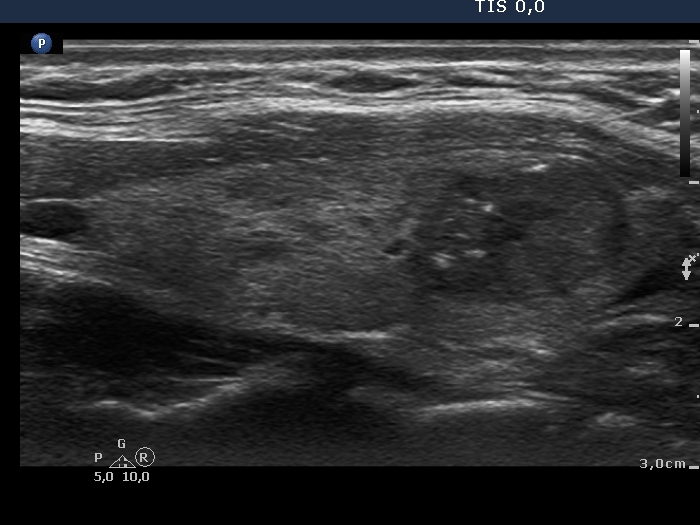

Second examination (second row of images):

Clinical presentation: The patient had no complaints.

Palpation: unchanged.

Functional state: euthyroidism (TSH 1.09 mIU/L).

Ultrasonography. The pattern remained unchanged.

Cytology resulted in Hashimoto's thyroiditis and suspicion of papillary cancer.

Total thyroidectomy was performed. Histopathology disclosed a T1b stage, encapsulated papillary cancer and Hashimoto's thyroiditis.

Comment. As a rule, we did not expect a malignant transformation of a benign nodule. The issue is the failure of FNA. In a nodule presenting suspicious ultrasound characteristics, repeat FNA is suggested even if the original cytological report was reassuring.